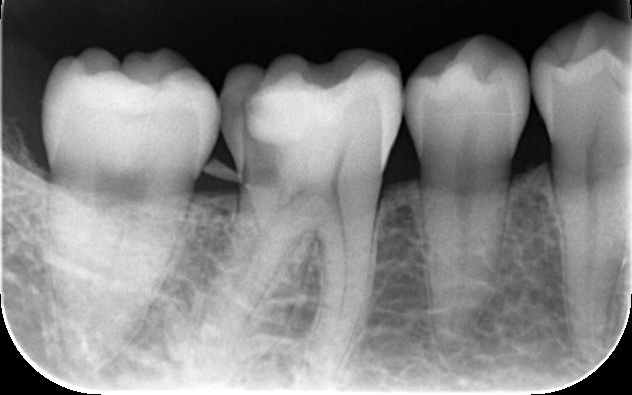

| カウンセリング | 拝見したところ、右下奥歯には歯槽骨(歯を支える骨)の近くまで進行している虫歯が認められました。通常の虫歯治療では、治療が困難な状態です。

このまま治療を行うと被せ物と歯の境目が歯茎の中に埋もれてしまい、結果として細菌が侵入しやすい状態になり、虫歯や歯周病のリスクが高まってせっかくの治療が長持ちしないおそれがあります。 以上のことから、歯の境目を歯茎の上に出す処置を行ってから、虫歯を治療する必要があると診断しました。 |

歯茎を一時的に切開して健全な歯質を適切な位置に露出させ、歯茎の高さを調整して被せ物と歯の境目を歯茎の縁より上に出す「歯周外科手術」を提案しました。

この治療は歯周病の再発リスクを大幅に減らし、長期間安定した状態を保つことができる方法です。 まずは歯周外科手術を行い、歯槽骨を必要な分だけ慎重に除去します。その後、健全な歯質が骨の縁から約3mm上に位置するよう精密に調整し、細菌の侵入を長期間防げる状態に整えました。 手術後は、歯茎と骨の状態が安定するまで経過観察を行い、十分に治癒したことが確認できたあと、顕微鏡を使用した「精密根管治療」を実施します。 続いて、歯の土台となるファイバー支台(ファイバーコア)を作製します。 土台が完成したあとは、被せ物を作製するための精密な型取りを行います。 最後に、完成したジルコニアセラミッククラウンを装着し、噛み合わせや見た目などに問題がないことを確認して、治療を終了しています。 |

歯周外科手術を行いました。